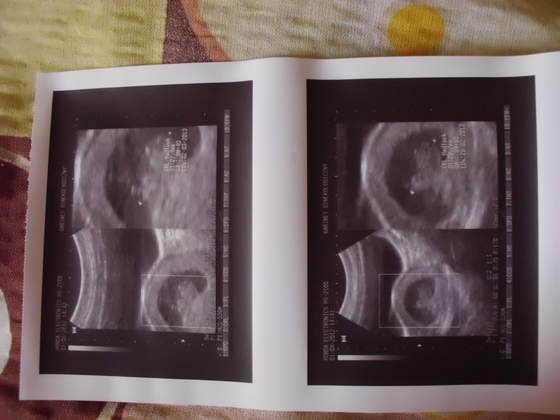

IMG_0453.jpg IMG_0454.jpgIMG_0455.jpgIMG_0456.jpg przedstawiam wszystkim cioteczką z bb moje małe szczęście:)